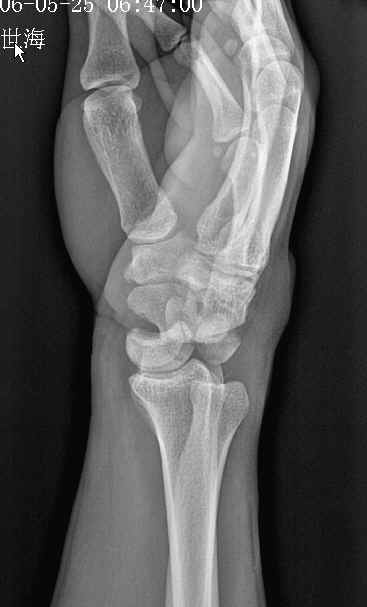

男,36岁,外伤后左腕部肿痛2小时。

左舟骨骨折伴有左月骨半脱位。

考虑:1、左舟骨骨折;

2、月骨半脱位;

3、软组织内金属异物。

2). 经舟骨月骨脱位:除月骨脱位外,同时伴有舟骨骨折,且骨折近段随月骨一起向前脱位,骨折远段仍处于原位置。

4 ).经舟骨月骨周围脱位:表现为月骨周围脱位拌舟骨骨折,且骨折远段随头骨向后脱位,而骨折近段与桡骨、月骨关系保持正常。

此例我感觉是“经舟骨月骨周围脱位”,我曾发布过一例,如下图:

我赞同是1、“经舟骨月骨周围脱位”,表现为月骨周围脱位拌舟骨骨折,且骨折远段随头骨向后脱位,而骨折近段与桡骨、月骨关系保持正常。2、软组织内金属异物。